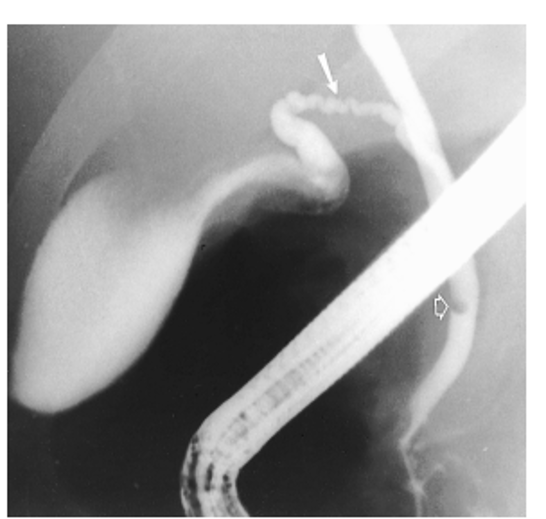

todani type III = choledococele at the intraduodenal bile duct

“cobra head”